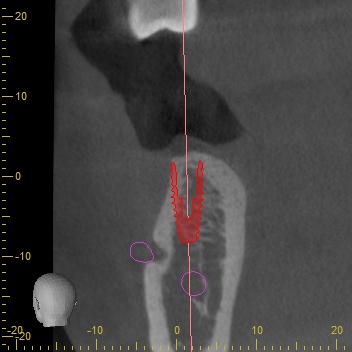

CTスキャンによるシュミレーション

永久歯がもともとないところは骨のボリュームが足りないことがほとんどです。

今回もCTスキャンで調べるとインプラントの外側に骨が足りないことが分かりました。足りない量がそれほど多くなかったためにインプラント埋め込みと同時に骨補填材を移植して骨造成をすることになりました。

骨造成での対応

今回はインプラント埋め込みと同時に骨補填材量をメインに移植することで骨造成を行いました。外側に骨を増やす骨造成という治療法は術後1週間ほど腫れますが、痛みは最小限で済みました。